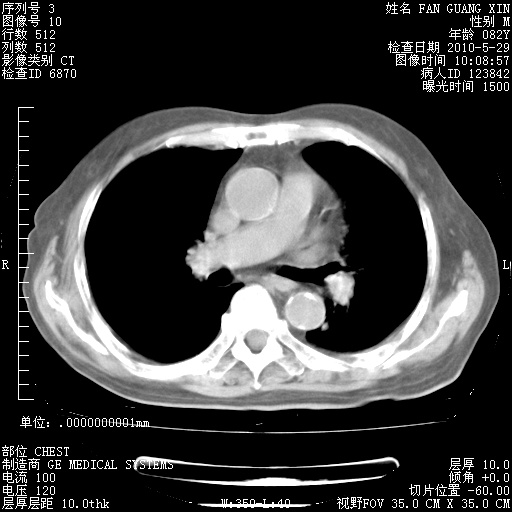

再治疗10天后的肺部CT 纵膈窗

阅读此次胸部CT,肺间质渗出性改变较入院时有吸收。目前从体温、白细胞、中性分叶明显增高,肯定存在细菌感染(发生医院感染哦,若无消化道及泌尿系统等感染的依据,肺部感染可能大)。若你院头孢哌酮舒巴坦钠耐药率较高,同意你的方案,若48小时体温仍高,可考虑使用碳青霉稀类抗菌药物,同时可予超声雾化、注意滴数时加大液体量。白蛋白33.30g/L较低哦,需加强营养等支持治疗。